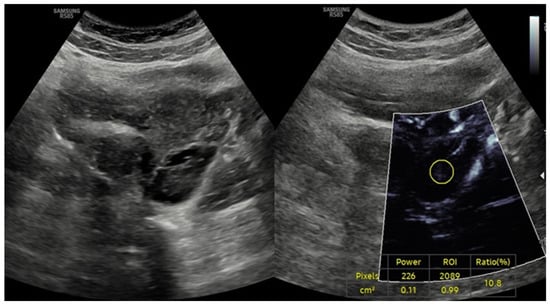

- Gray-Scale Ultrasonography (USG): A Samsung RS85 Prestige Ultrasound System (Samsung Medison) with a convex transducer (CA1-7A, 1–7 MHz) was utilized to perform gray-scale ultrasonographic assessment. The evaluation of each ovary involved a systematic examination for polycystic ovarian morphology (PCOM). This condition was characterized by either the presence of 20 or more follicles with diameters ranging from 2 to 9 mm, or an ovarian volume greater than 10 cm3.

- Doppler Examination (MV-Flow, MVI): Ovarian stromal vascularity was evaluated using the same ultrasound equipment and transducer (Samsung RS85 Prestige with CA1-7A, 1–7 MHz). MV-Flow Doppler imaging was performed consistently in the longitudinal plane to maintain anatomical standardization. Cine-loop clips of at least 3 s duration were captured and stored. For vascularity index measurements, the optimal frame demonstrating clear vascular flow was selected from the stored cine-loop clips. In the ovarian stroma, three circular regions of interest (ROIs) were centrally positioned. These ROIs, each with a fixed 5 mm diameter, were carefully selected to exclude dominant follicles and peripheral vascular structures. The ROI dimensions and MV-Flow Doppler imaging parameters, including pulse repetition frequency (PRF), gain, and wall filter, were maintained consistently throughout the duration of the study.